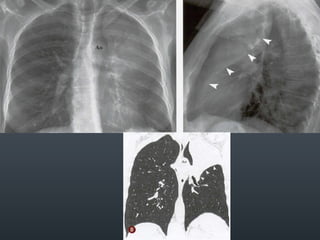

O documento discute vários conceitos radiológicos incluindo consolidação, atelectasia, nódulos, pseudocavidades e padrões intersticiais, fornecendo definições, sinais e diagnósticos diferenciais para cada tópico. Ele também discute a redução da atenuação pulmonar e fornece um link para mais informações.